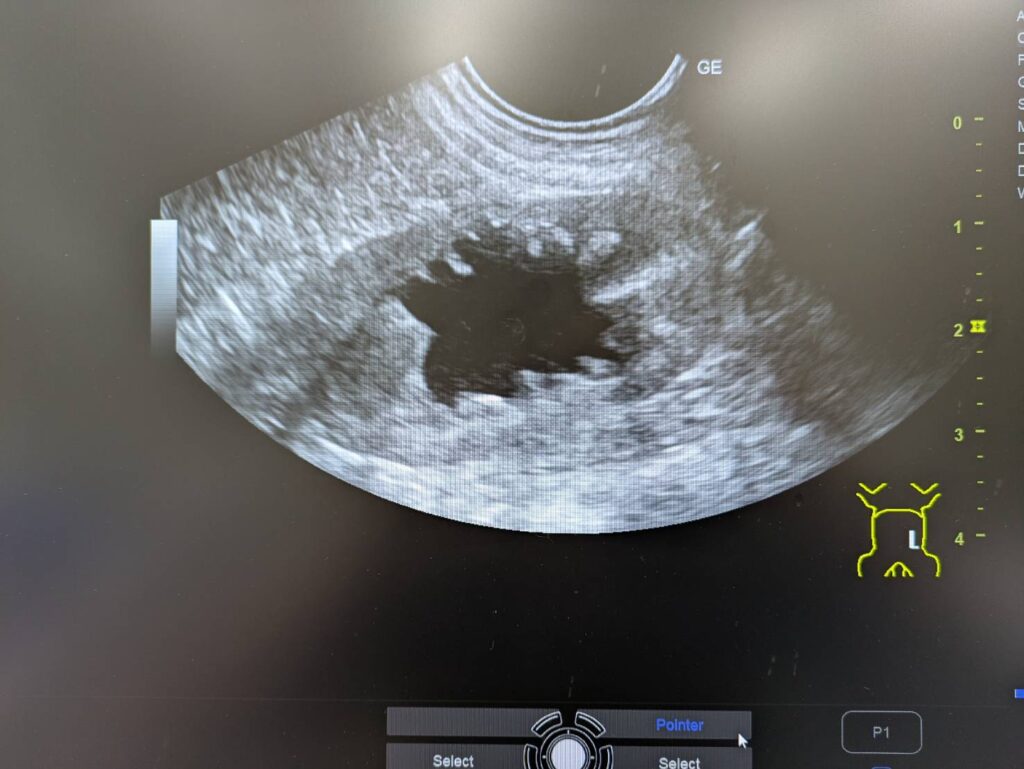

結果はこんな感じ。

左の腎臓の腎盂が重度に拡張し

その先の尿管内に結石のようなものがみつかりました。

診断は尿管閉塞による急性腎障害といった感じでしょうか。